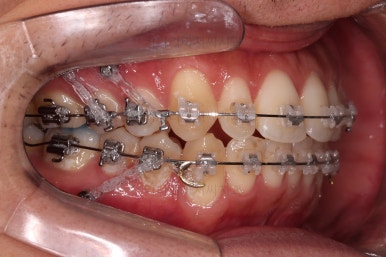

한참을 셋팅한 방향으로 치열을 당겨줍니다.

중간평가를 자주 하게 됩니다.

입을 다물었을 때 턱끝이 점점 자연스러워지는 느낌이네요. 윗입술 부위가 둥글게 돌출되어 보이던 느낌도 점점 좋아지고 있고요.

아직은 환자분이 개선을 더 원하기 때문에 현재의 방식으로 더 진행하기로 했습니다.

옆모습은 상당히 만족하고 계셨고, 웃을 때의 치열의 중앙선을 좀 더 맞추고 싶어하셨습니다.

여러 가지를 더 원하시는 만큼 개선한 뒤 부산연제구교정 치료를 마무리하기로 했습니다.